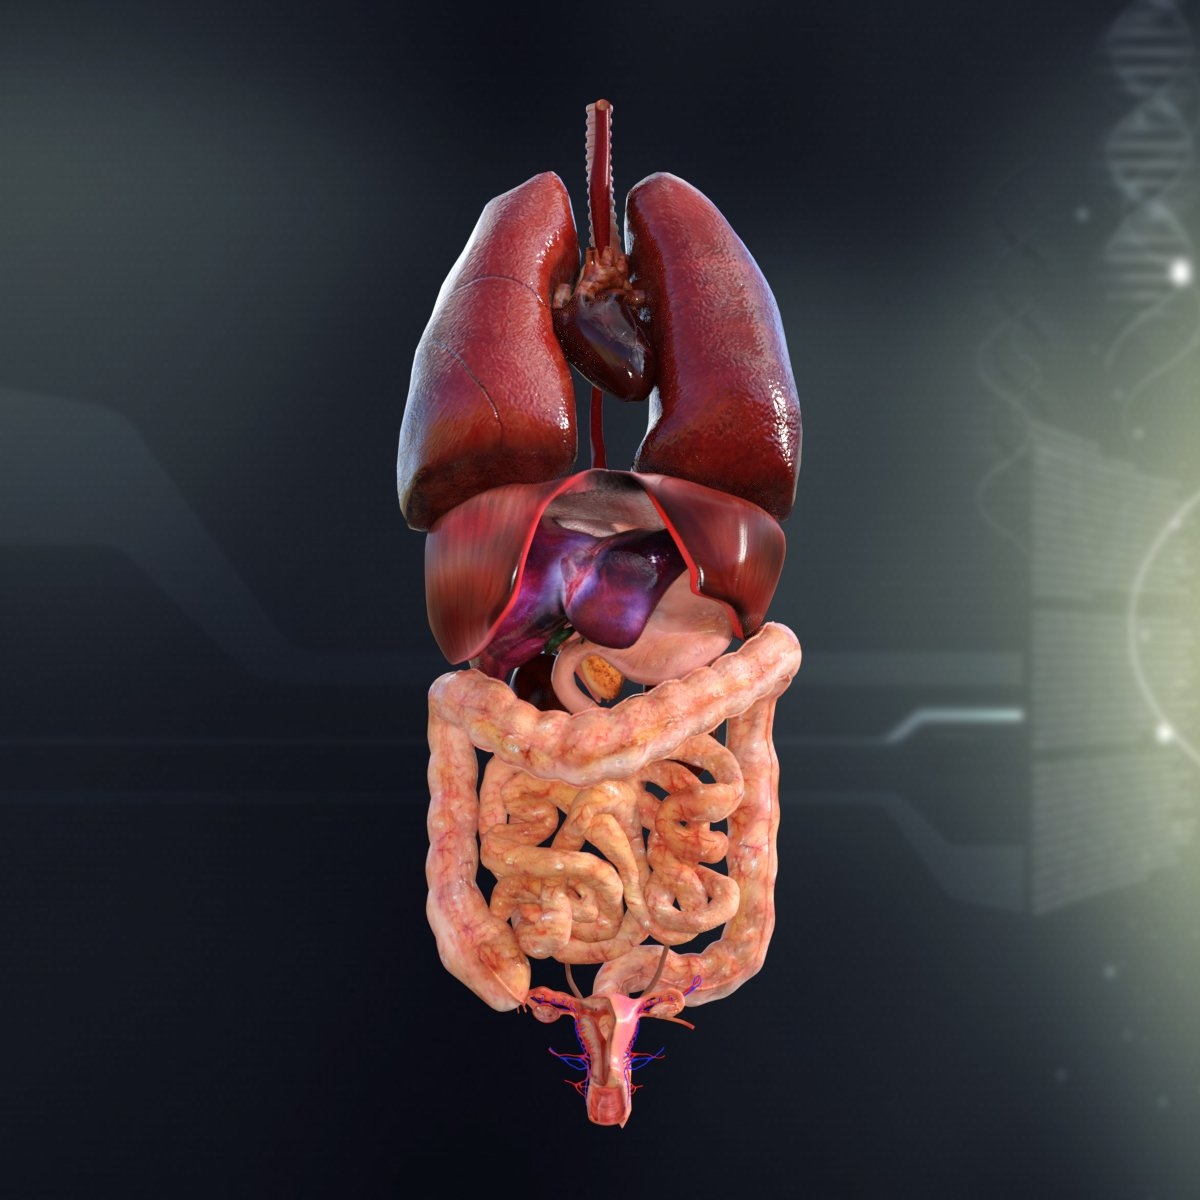

Anatomy Of Internal Organs Female – Organ Anatomy Female Anatomy …

Right Side Women’s Body Human Body Organs / Human Anatomy And …

Female Body Organs Diagram Anatomy | MedicineBTG.com

Human Anatomy Picture Organs Female Human Body Diagram Of Organs See …

Female Human Organs Diagram | MedicineBTG.com

Internal Organs Adult Female Front And Back View Stock Photo – Download …

Illustration Of Female Internal Organs Photograph by Science Source

Illustration Of Female Internal Organs Photograph by Science Source

Illustration Of Woman\’S Internal Organs / Internal Human Organ Ovaries …

Human Female Organ Diagram . Human Female Organ Diagram Colorful Human …

3dsmax human female internal organs

Female Internal Organs, Artwork Photograph by Roger Harris

Human Female Internal Organs Anatomy 3D Model MAX OBJ 3DS FBX C4D LWO …

3D whole-body frontal view with semi-transparent skin (left) and major …

女性内脏3D模型 – TurboSquid 966689